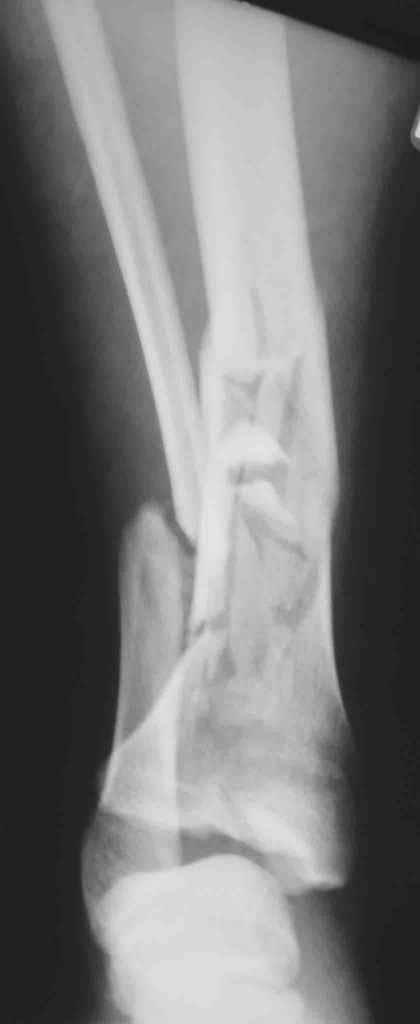

Re: Открытый оскольчатый внутрисуставной перелом дистального отдела большеберцовой кости

Смирнов Алексей 17 Март 2006, 21:51

Вот что получилось